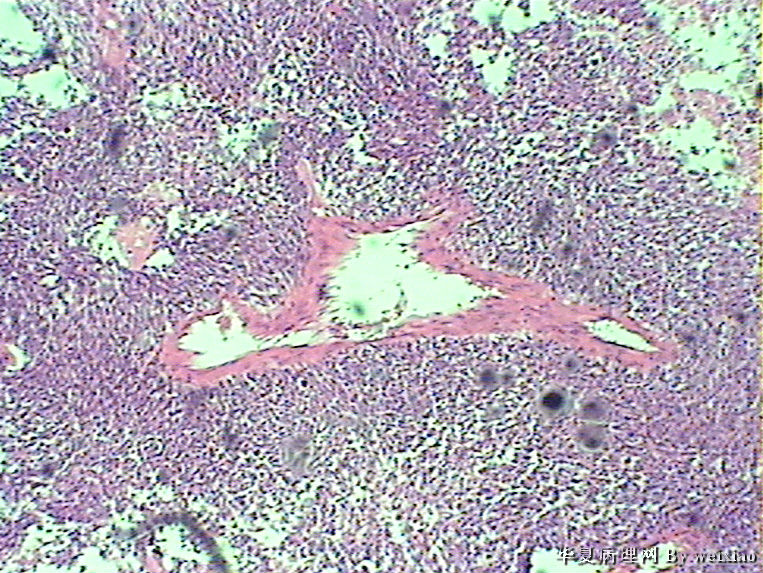

病史:男45岁,头痛2个月,手术所见:额叶占位性病变,与周围正常脑组  织的界限不清。

大体:灰白色碎组织一堆,质软,大小:2.5*1.8*1.3cm

• 额叶肿瘤图3

图3

×参考诊断

胶质母细胞瘤

The tumor cells are kind of spindle, need to rule out gliosarcoma, you need to check MRI films, do immunostain for GFAP, and vimentin. The vascular proliferation (VP) supports GBM.

肿瘤细胞呈梭形,血管增生明显,有坏死,符合胶质母。